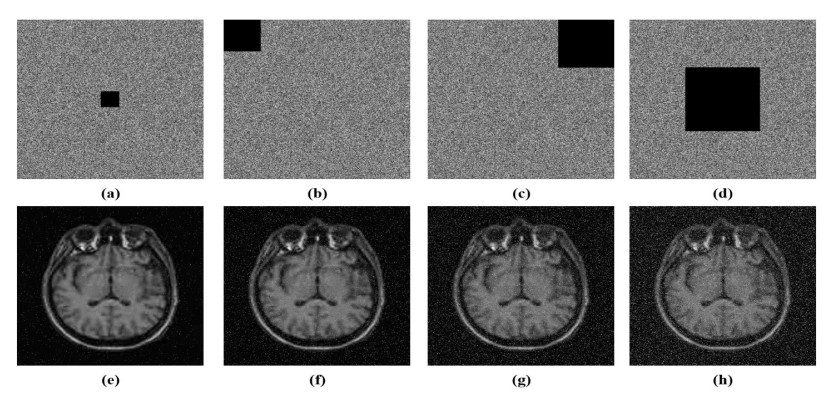

• Safeguarding medical images against unauthorized access and alteration during storage and transmission is a critical challenge in modern telemedicine systems. This paper introduces a robust method to encrypt medical images in which the confusion stage is driven by a four-dimensional (4D) fractional-order chaotic system, and the diffusion process utilizes a symmetric matrix integrated with a one-dimensional (1D) chaotic map. The fractional 4D chaotic system reveals intricate dynamic behavior and is extremely sensitive to initial conditions, which enhances the confusion capability by thoroughly scrambling pixel positions. The symmetry matrix is combined with a generated chaotic sequence from a 1D chaotic map during the diffusion process that ensures strong pixel intensity diffusion and key dependence. Numerous experiments carried out on a variety of medical images confirm the outstanding performance of the suggested method. The suggested method features a key space exceeding 2100, exhibiting significant robustness to brute-force attacks. It achieves unified average changing intensity (UACI) values above 33% and number of pixels change rate (NPCR) values exceeding 99.6%, confirms robustness to differential attacks, and successfully resists chosen-plaintext and known-plaintext attacks. Additionally, the low pixel correlation and uniform histograms, along with average values of information entropy of 7.9973 and 7.9993 for 256×256 and 512×512 images, respectively, demonstrate strong resilience to statistical attacks. Furthermore, robust evaluations against cropping and noise attacks demonstrate the scheme's practical security, highlighting its suitability for the safe storage and transmission of medical images in healthcare applications. Compared with related methods, the suggested method offers superior security performance.